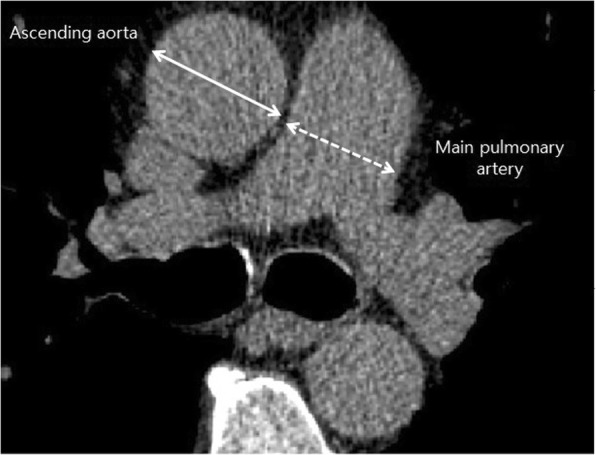

CT scans of the chest were performed in all the patients at the time of initial diagnosis of IPF. The diameter of the mPA and that of the ascending Ao were measured at the level of bifurcation of the pulmonary artery. The diameter of the mPA was defined as the widest diameter perpendicular to the long axis of the mPA and measurement of the ascending Ao was taken as the transverse diameter (Fig. 1). Two reviewers who were blinded to the clinical data measured the mPA and Ao on the same CT image independently, and the average of two measurements was used to calculate the mPA/Ao ratio. The value of inter-observer correlation coefficient was 0.84 (95% confidence interval (CI), 0.80–0.87) for mPA, and 0.92 (95% CI, 0.90–0.94) for Ao.

Fig. 1.

Measurement of the main pulmonary artery (mPA) and ascending aorta (Ao) diameters at the level of bifurcation of the pulmonary artery. The diameter of the mPA was defined as the widest diameter perpendicular to the long axis of the mPA and measurement of the ascending Ao was taken as the transverse diameter